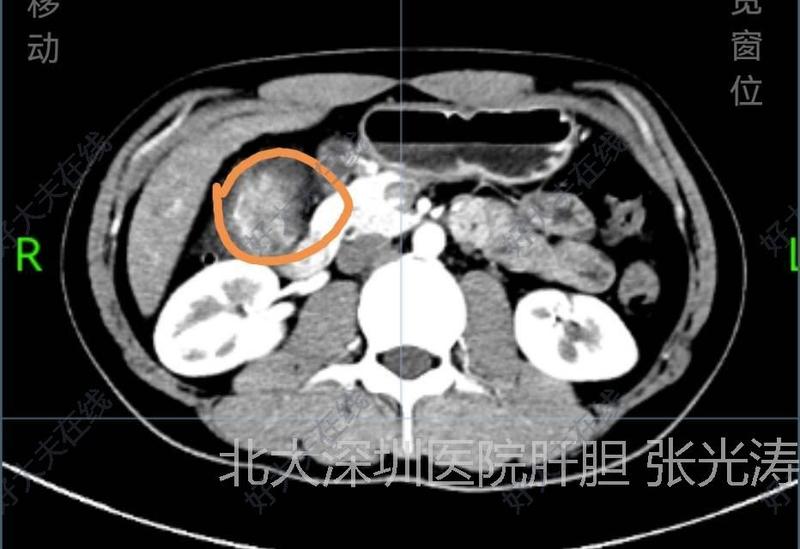

治療前 患者因右上腹疼痛2月入院。查CT提示膽囊底部占位,36*35mm,不除外膽囊癌可能。腫瘤標志物正常。術(shù)前按膽囊癌術(shù)前準備。 治療中 術(shù)中發(fā)現(xiàn)膽囊底部較大腫塊,完整切除膽囊,完整取出。膽囊底部囊壁明顯增厚。術(shù)中快速病理為膽囊腺肌癥。 治療后 治療后1天 患者今天術(shù)后第一天,恢復飲食,下床活動。